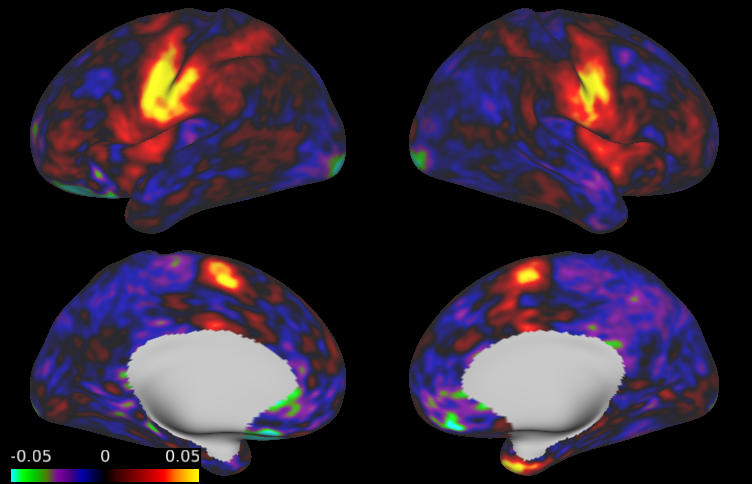

Figure LABEL:fig:app:beta_subj displays the Bayesian estimates of activation amplitude (posterior means) for the visual cue and tongue tasks, along with the classical GLM estimates, for one randomly selected subject. The remaining tasks are shown in Appendix C. Both sets of estimates are noisy, due to the high levels of noise in fMRI data and relatively short duration of the tasks performed for each individual subject (303030 seconds for the visual cue; 242424 seconds for the tongue task); however, the Bayesian estimates are substantially smoother than the classical estimates, even though the data was smoothed prior to fitting the classical GLM but not the Bayesian GLM. Figure LABEL:fig:app:beta displays group-level estimates of activation amplitude based on the classical and Bayesian GLM approaches. For the Bayesian GLM, the results using the joint modeling approach and the two-level modeling approach with the sampling method described in Section 3.1 are both displayed. In both the subject-level and group-level estimates, the activation fields for each task are generally as expected: during the visual cue, the visual and orbitofrontal (decision making) regions are highly active, while the somatomotor (motor planning) region is activated to a lesser degree; during the tongue movement task, the area of the motor cortex associated with the tongue shows a strong degree of activation; and the remaining motor tasks activate the expected areas of the motor cortex (see Figures S4 and S5 in Appendix C). Compared with the classical GLM, the Bayesian GLM results in smoother estimates of activation, as it accounts for dependence in the degree of activation between neighboring locations. As hypothesized, the two-level modeling approach tends to result in somewhat oversmoothed estimates, compared with the joint modeling approach.

Figure LABEL:fig:app99 shows the regions of activation identified by thresholding the joint PPM excursion function for each task, along with those identified through the classical GLM with FDR and FWER correction, using significance level 0.010.010.01 in each method. For the Bayesian GLM, regions of activation at activation threshold γ=0𝛾0\gamma=0 are shown in purple, while those at γ=0.027𝛾0.027\gamma=0.027, corresponding to 1%percent11\% of the global baseline signal, are shown in red. Several effects are clearly notable. First, the areas of activation based on controlling the FWER in the classical GLM are very conservative. This is a well-known issue with this approach that worsens as the number of locations increases, which is likely why FWER correction produces reasonable results in the simulation study but very conservative results on real fMRI data. FDR control results in significantly larger areas of activation, reflecting an increase in power while maintaining a known degree of false positive control. Second, the areas of activation based on γ=0𝛾0\gamma=0 in the Bayesian GLM are similar to those based on FDR control in the classical GLM, but are smoother and somewhat larger. This likely reflects an increase in power resulting from incorporating spatial dependencies in the Bayesian GLM, as observed in our simulation study. Third, compared with the joint model, the areas of activation based on the Bayesian two-level model are smoother but similar in size. This illustrates that while the two-level approach tends to result in somewhat oversmoothed estimates, the sampling method described in Section 3.1 is able to appropriately account for uncertainty in the subject-level estimates when fitting the group-level model. Finally, the increased power in the joint PPM results in widespread areas of activation based on γ=0𝛾0\gamma=0, while the more biologically meaningful threshold of γ=0.027𝛾0.027\gamma=0.027 (1%percent11\% of the baseline signal) results in more conservative areas of activation that correspond well to the highly activated areas shown in yellow in Figure LABEL:fig:app:beta.

These results illustrate the benefits of using a Bayesian framework to account for spatial dependencies in fMRI task activation studies. Compared with the traditional analysis techniques, the proposed Bayesian GLM approach results in smoother estimates of activation for individual subjects and groups of subjects, smoother active regions, and greater power to detect areas of activation, particularly more subtle activations.